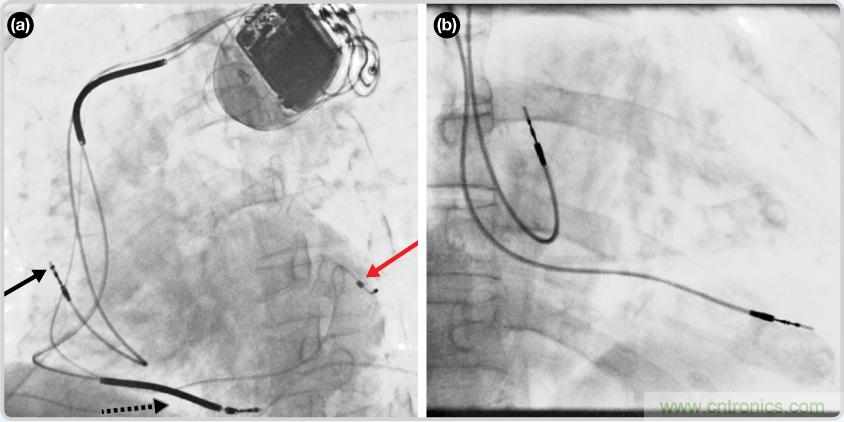

CRT器件在圖4(a)中的透視圖像中可以看見。醫師就是利用這種影像來放置導聯線的。對于非專業人士來說,這種影像是很難解讀的??梢钥吹叫呐K淡淡的輪廓——這是搏動中的心臟的靜態視圖。起搏器位于右心房上,心臟頂點指向右下方。在這個典型的導聯線放置實例中,黑色箭頭指向右心房導聯線。虛線黑色箭頭指向右心室導聯線。紅色箭頭標示的導聯線只能看到一部分,這是左心室導聯線(紅箭頭指向電極尖端)。圖4(b)展示的是雙腔起搏器的典型導聯線放置透視圖像。右心房導聯線指向上方,置于右心房中。右心室導聯線則位于右心室頂部。

圖4. 起搏器導聯線放置的透視圖像3 (a). 單腔起搏器;(b).雙腔起搏器